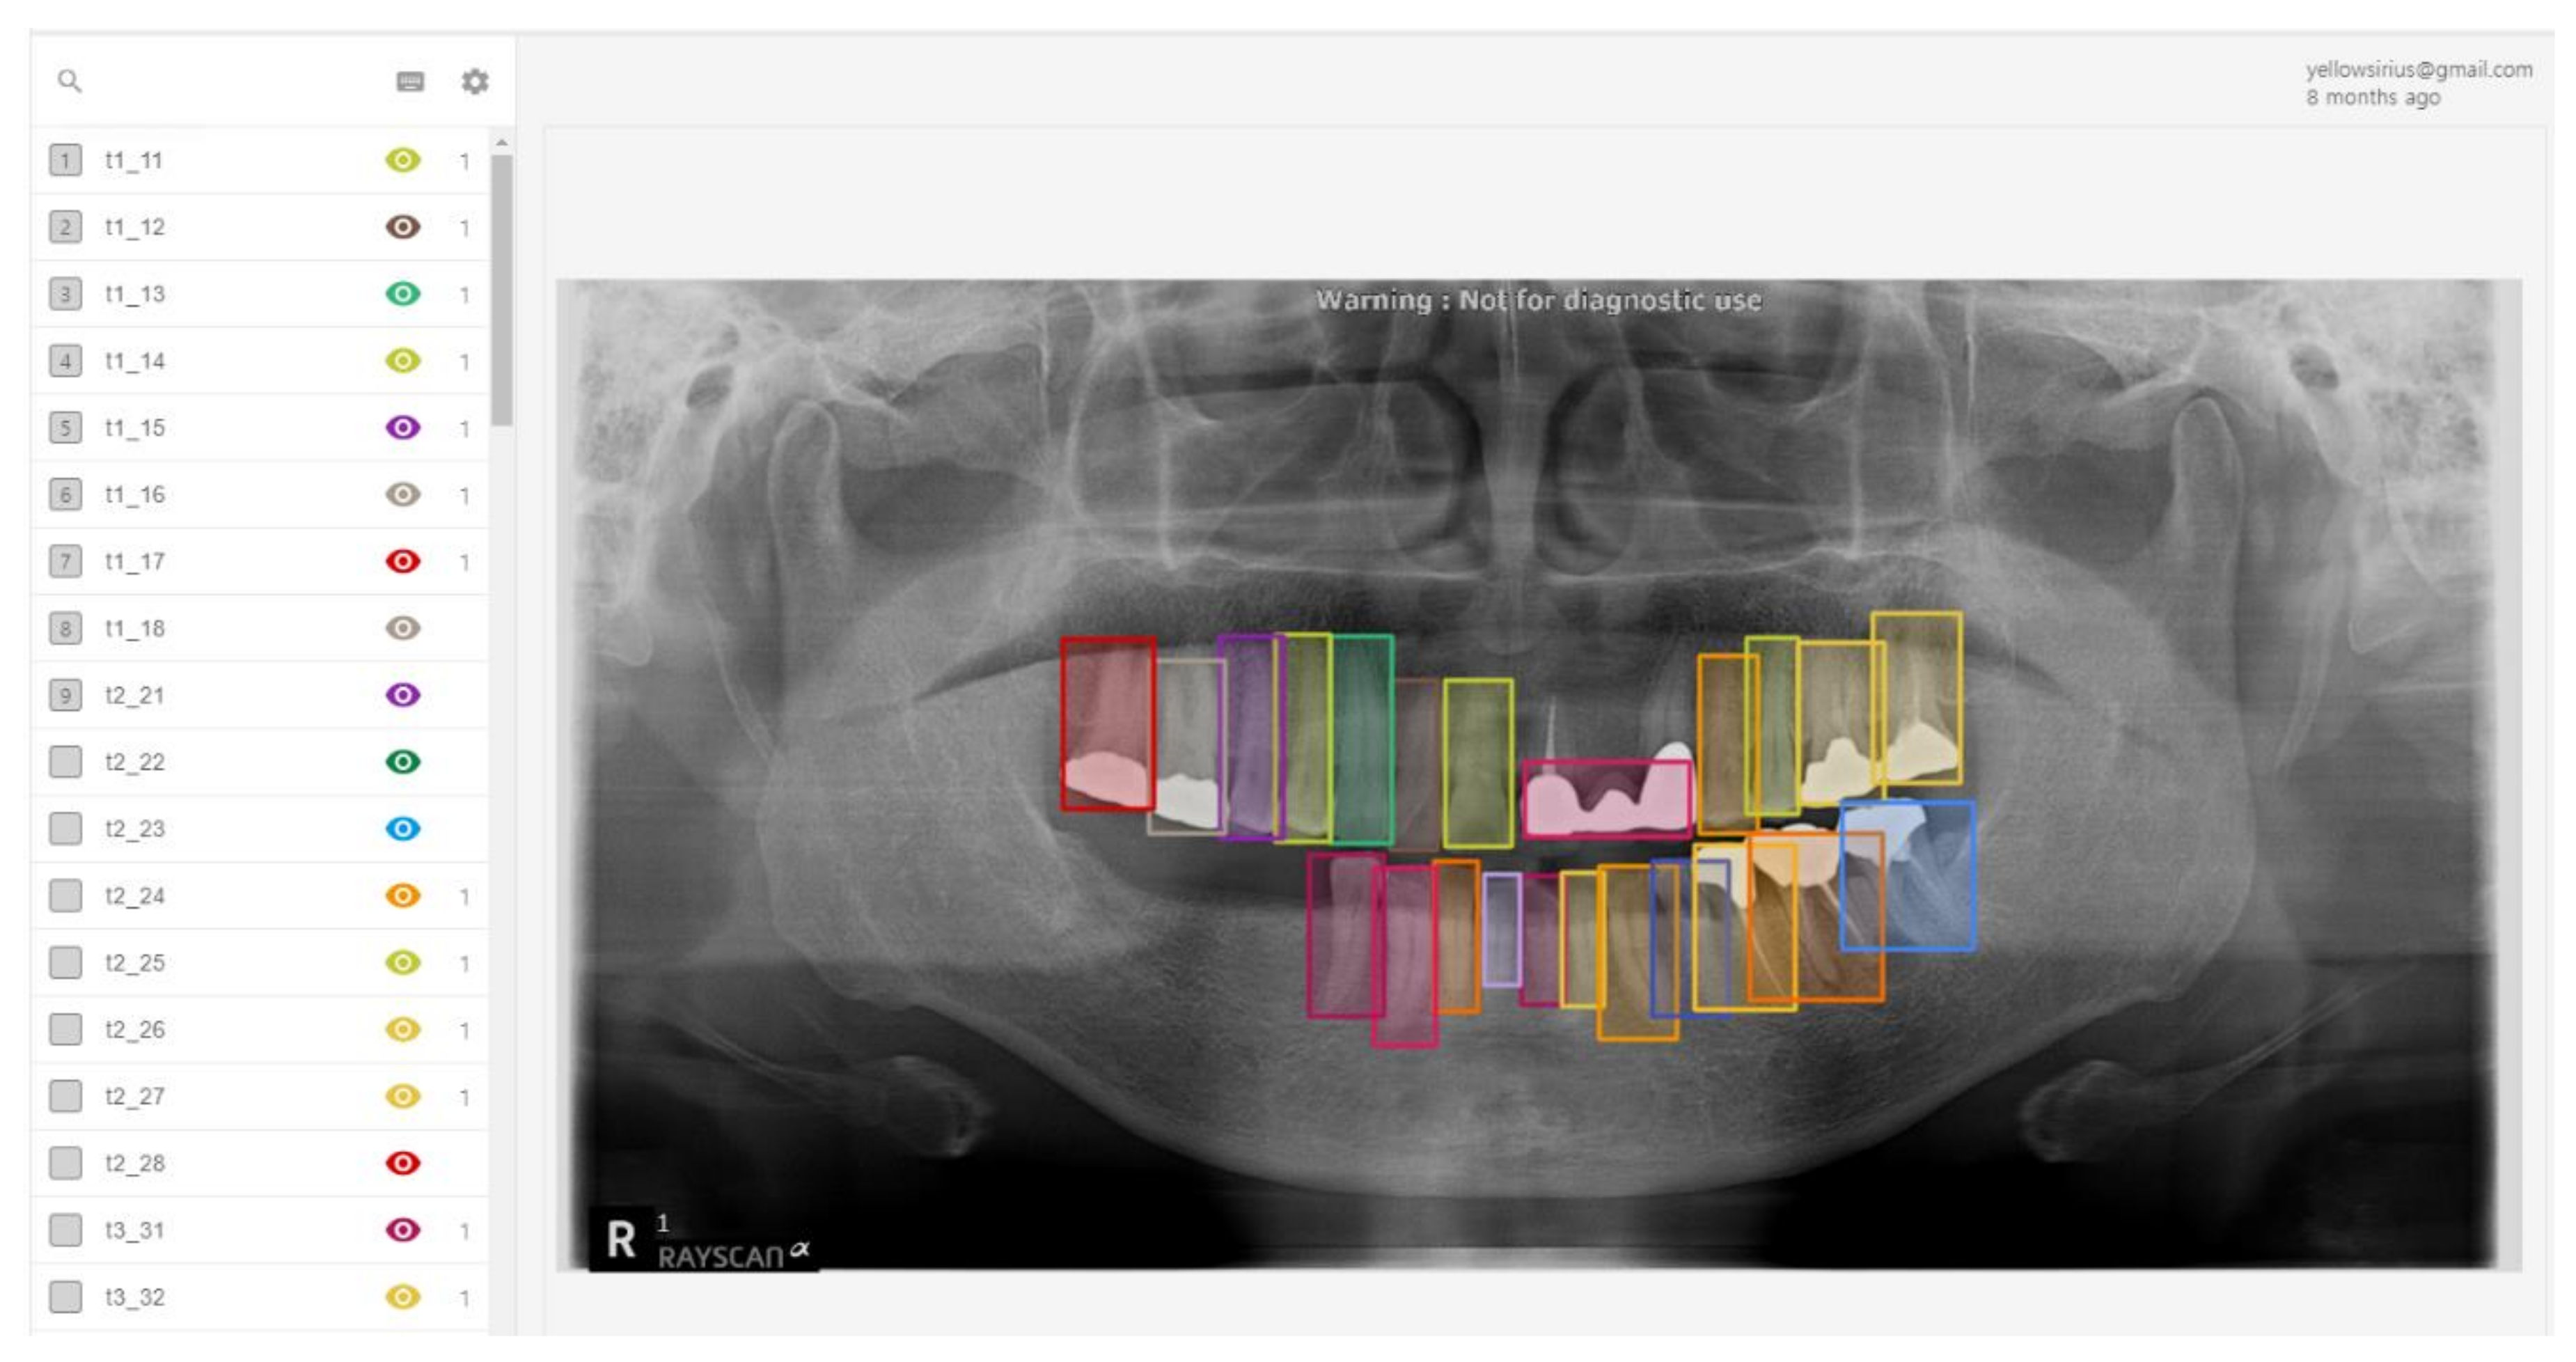

A total of 303 panoramic patient data were collected from the Medipartner Dental Network Hospital after obtaining patient agreements. Each image was anonymized and converted into a 1600 pixel × 900 pixel image in JPG format. Three dentists labeled each panoramic tooth image, using Label Box as the labeling tool. Figure 4 shows the labeling results on an image from the Label Box tool used by the dentists. Only labeled dental implants with fixtures were included in the data set because we did not have enough abutments and prostheses images on the dental panorama images.

For the tooth detection, teeth and implants were detected and parts of the root of one tooth and parts of two individuals were considered to be in different classes. The detailed execution method is shown in Figure 5. The objects in the panoramic image are mainly composed of implant fixtures, crowns, and teeth. Here, specific numbers are assigned to each tooth. Using such images, a total of 253 training sets and 50 test sets were obtained.

The labeled data were categorized as dental object detection information or tooth numbering information. The collected data are presented in Figure 6. In the image on the top-right of Figure 6, blue parts indicate the labeling data on the implant fixtures, and the orange parts indicate the data on the crowns. The tooth labeling information presented in the lower-right image in Figure 6 indicates the information used to label the individual tooth numbers.

Figure 4. Labeling tool used to generate training and test sets.

Figure 5. DPR labeling method.

Figure 6. Example of labeled data.